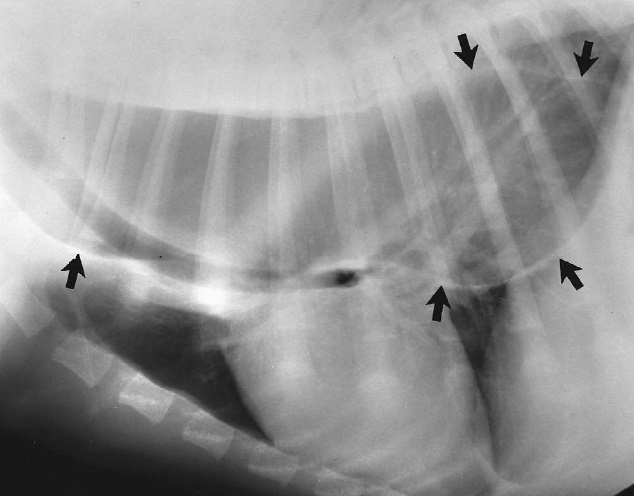

Врожденная кишечная непроходимость

Подход к пациенту с мегаколоном